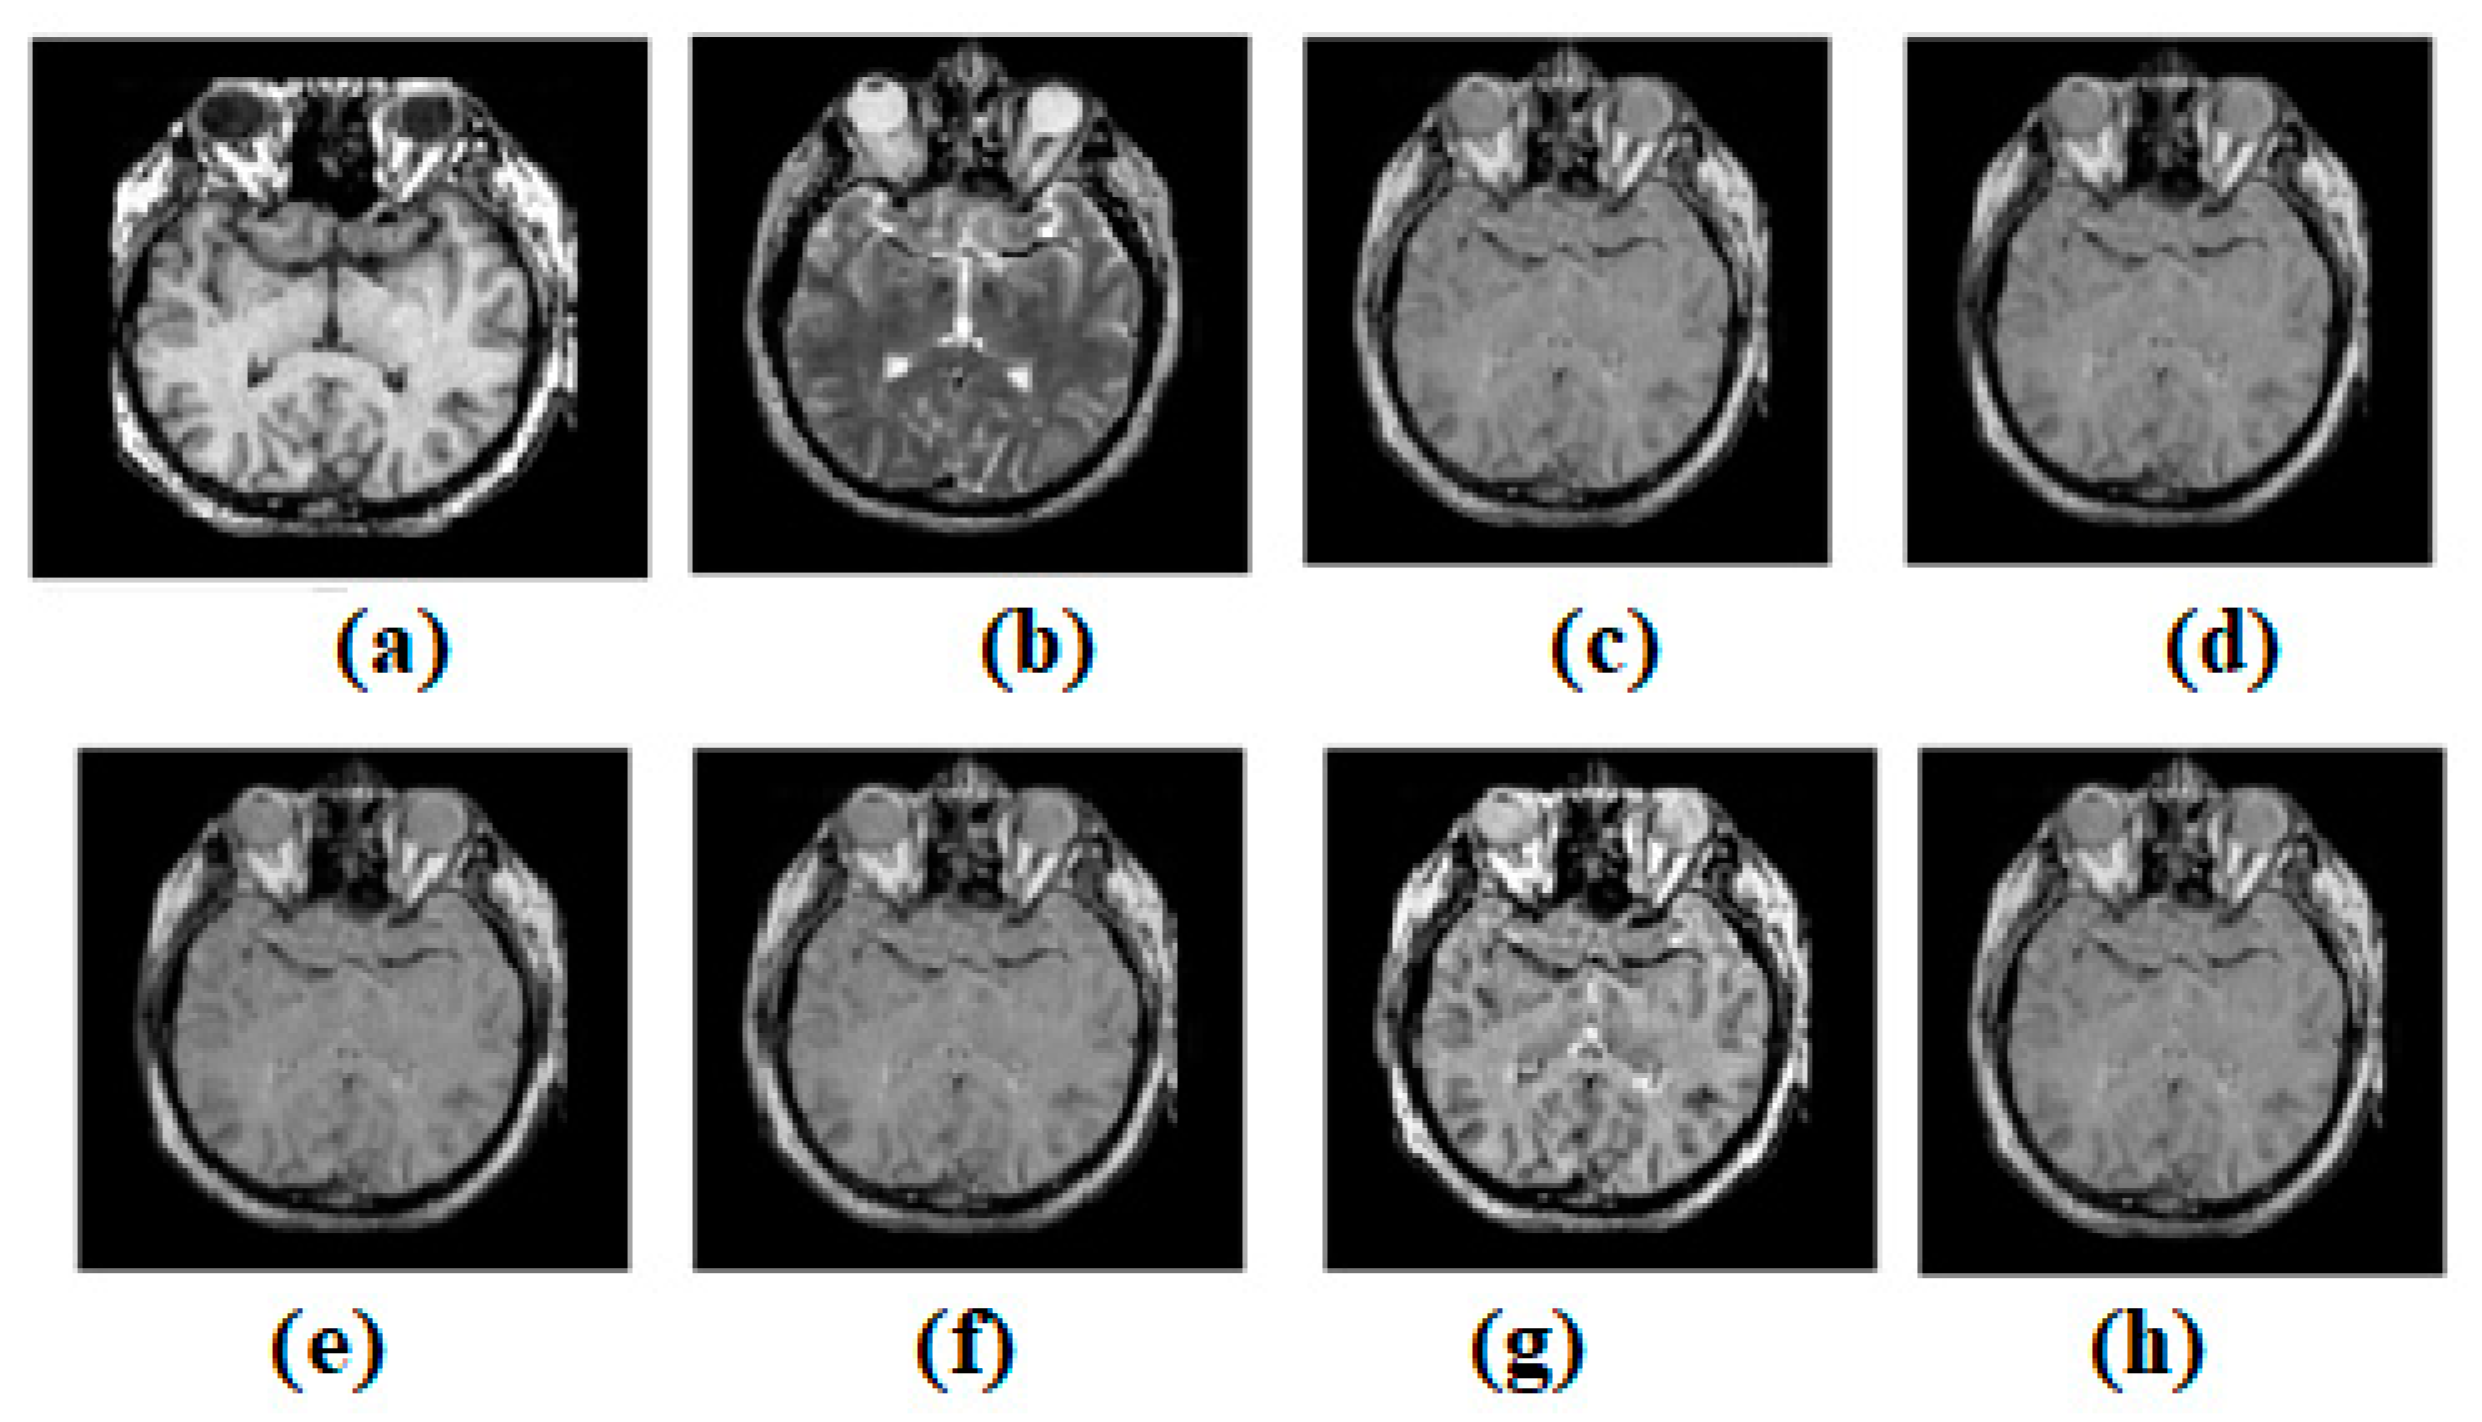

Figure 4.

Multi-modality medical image fusion results (a) Source image: CT, (b) Source Image: MR, (c) Result of [44], (d) Result of [47], (e) Result of [48], (f) Result of [49], (g) Result of [51], (h) Result of [53].

Figure 4a,b shows both the MR-T2 and SPECT images. These two images are combined into existing structures such as [44,47,49,51,53]. Figure 4c–g expresses the effects of [44,47,49,51,53], respectively. To test the most current methods, a different modality dataset is also used. As can be seen in Figure 4, the outcome of ref. [44] is acceptable, but it falls short when it comes to preserving edges and textures. However, distinctions remain clear. There are several consistent spots where the original texture has been maintained. However, there is a lack of clarity in a wildly varying domain. Figure 4 shows that the output of ref. [47] is passable, but it fails to meet expectations when it comes to edge and texture preservation. However, the contrasts are excellently preserved. Some places are consistent, and the texture has been well-preserved overall. The heterogeneous region, however, suffers from a severe shortage of illumination. While the result of ref. [49] in Figure 4 is satisfactory, it falls short when it comes to the preservation of edges and textures. The contrasts of ref. [48], however, have been retained very well. Some areas are consistent, and the original texture has been maintained with great care. The texture shifts are not limited to these spots. However, the light levels are inadequate in the area of heterogeneity. The output of ref. [51] in Figure 4 is good, but it falls short of expectations when it comes to preserving the image’s edges and textures. However, contrasts have been maintained to a satisfactory degree. Several areas of continuity have been achieved, and the texture has been preserved with great skill. In contrast, the area with uneven brightness is considered to be the heterogeneous zone. The output of ref. [53] in Figure 4 is acceptable, but it fails to maintain edges and textures. Nevertheless, the distinctions are quite well-preserved. In some spots, the uniformity of the surface has been maintained, and the texture, too, has been carefully preserved. The non-uniform region, however, has a low luminosity.